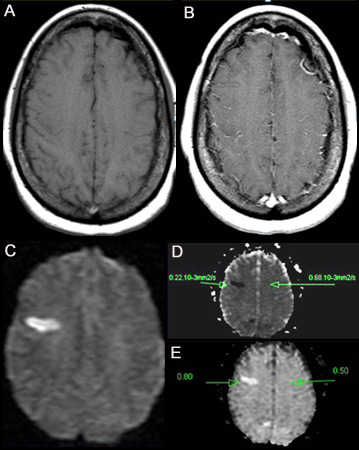

[Figure caption and citation for the preceding image starts]: (A) IRM ponderada en T1 sin contraste. (B) IRM ponderada en T1 poscontraste en que se observa un aumento mínimo de los vasos leptomeníngeos en la región frontal derecha. (C) Imagen ponderada en difusión (DWI) en que se observa un área hiper intensa en la región frontal derecha. (D) En el mapa de coeficiente de difusión aparente (ADC) se observa una lesión hipointensa, que indica difusión restringida que se correlaciona con alta intensidad en DWI y difusión exponencial. (E) El valor de ADC es 0.22 x 10³ mm²/segundo, correspondiente a un infarto hiperagudoDe la colección personal de Eric E. Smith; usado con autorización [Citation ends].